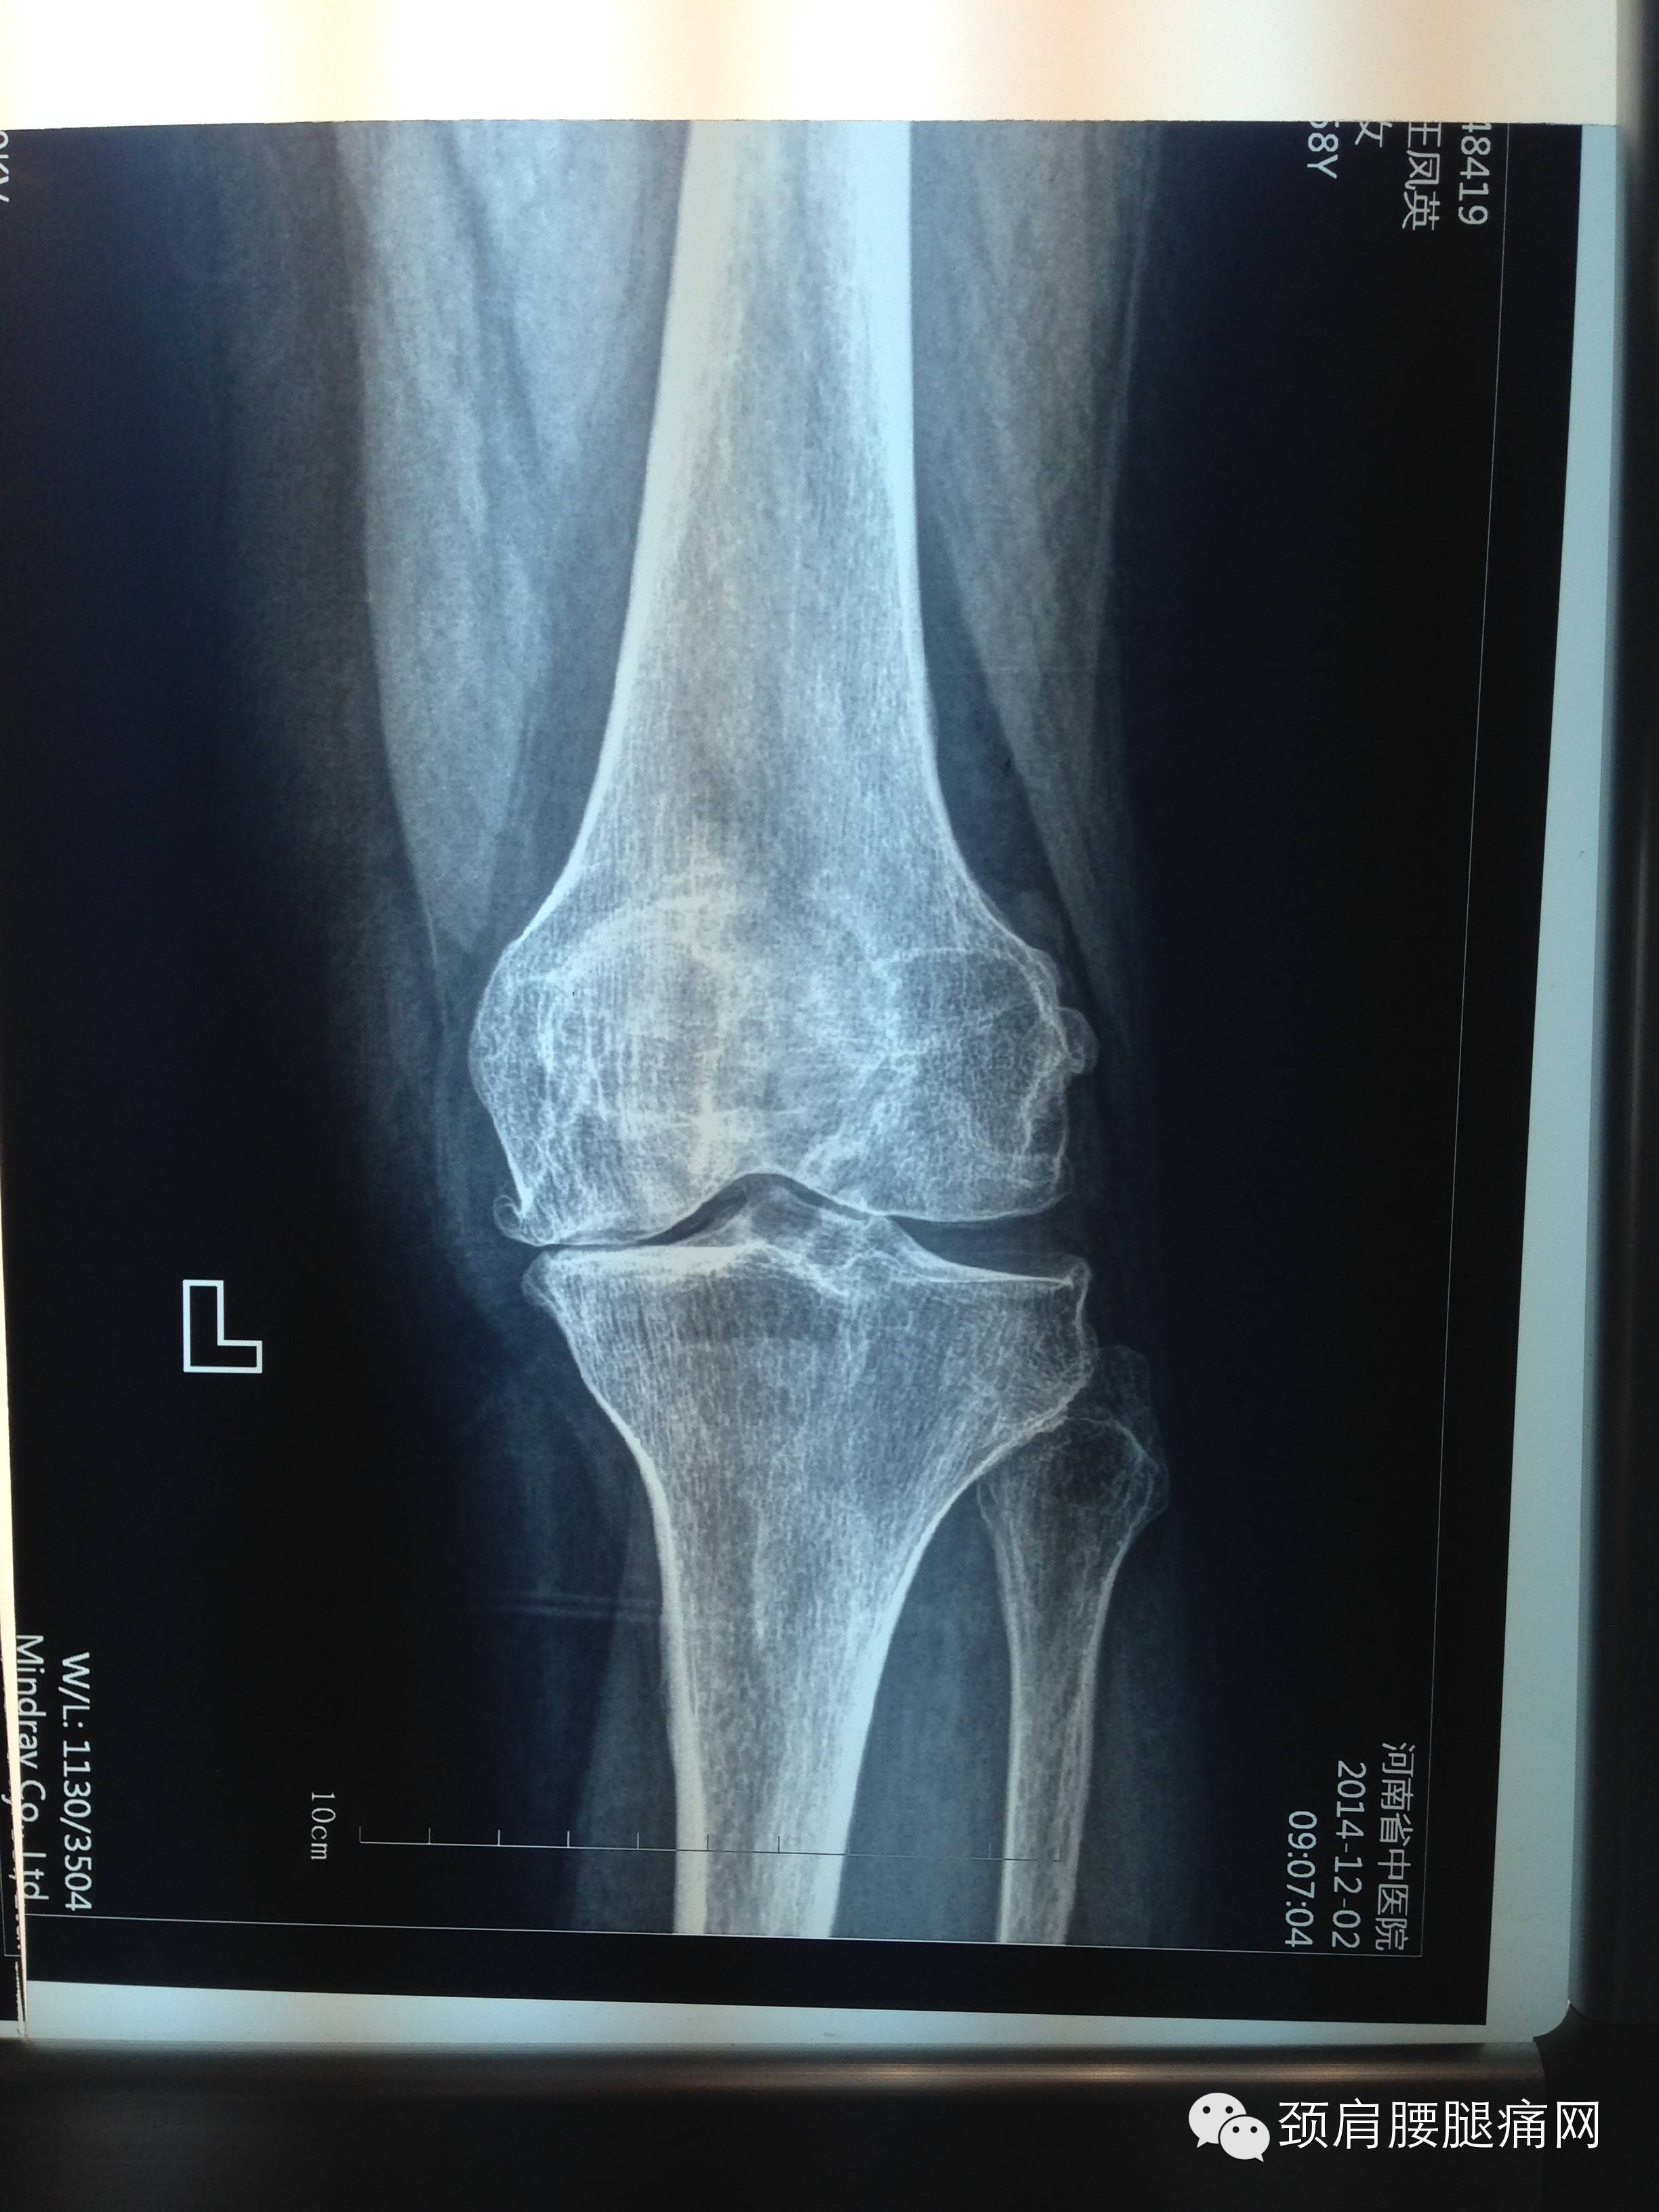

患者王某,女,58岁,郑州市金水区干部。双膝关节疼痛4年,现左膝关节强直(僵直),关节屈伸活动度仅有20度,行走困难,多家医院检查诊断为双膝关节重度骨性关节炎,建议人工关节置换手术治疗。

患者非常害怕手术,就来到河南省中医院疼痛科,王学昌主任采用弧刃针刀结合臭氧水治疗,如上视频。术中无激素、无麻药、患者无任何不适,术后患者当即可以下地活动,膝关节活动度大幅改善至可屈曲膝关节120°,患者很是满意!